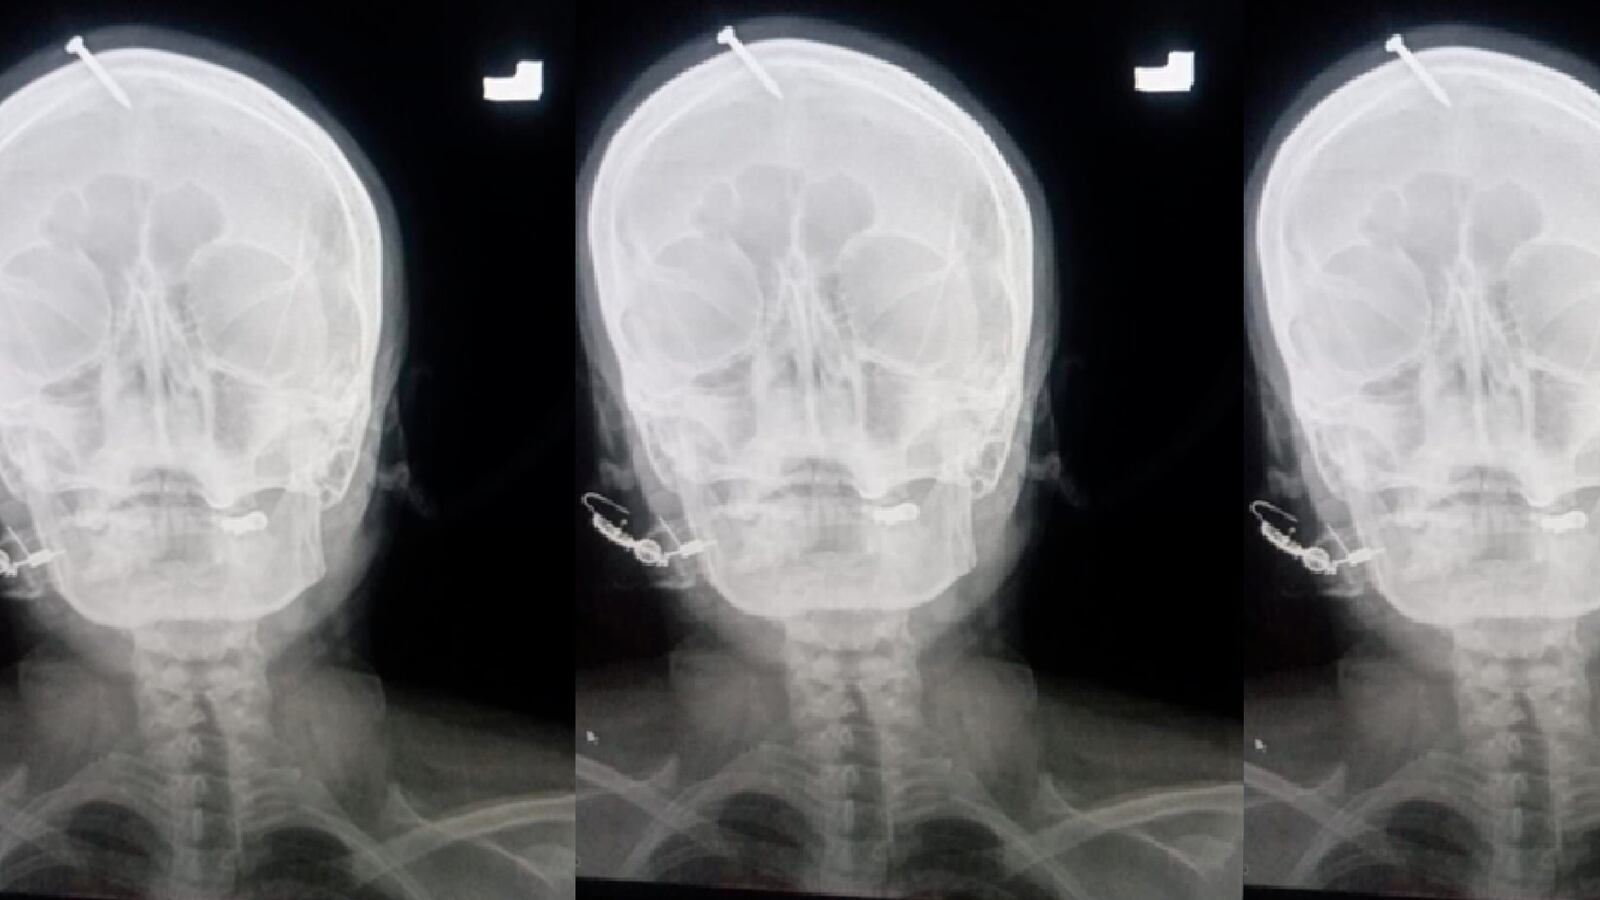

The pregnant woman was so desperate not to give birth to a fourth daughter that she consulted a faith healer, who said he knew just what to do: Hammer a two-inch nail into her skull.

The woman, who has not yet been identified by police, showed up at the Lady Reading Hospital in Pakistan this week with extensive bleeding from her skull. She at first told the Peshawar city medical staff she had been “advised” to recite chants and hammer the nail into her own skull to guarantee the gender of her unborn child would be male.

Peshawar police, who tweeted a photo of the pregnant woman’s skull with the nail intact, say they are using CCTV footage to try to to retrace the woman’s steps from the hospital to find the culprit. She left the facility immediately after the nail was removed. “The process of identifying the victim from the CCTV footage as well as from the computer entry data is underway,” police tweeted. The local police captain said a special team had been assembled to bring justice to the fake healer “who played with the life of an innocent woman and put a nail in her head with [the] false promise of a male child.”